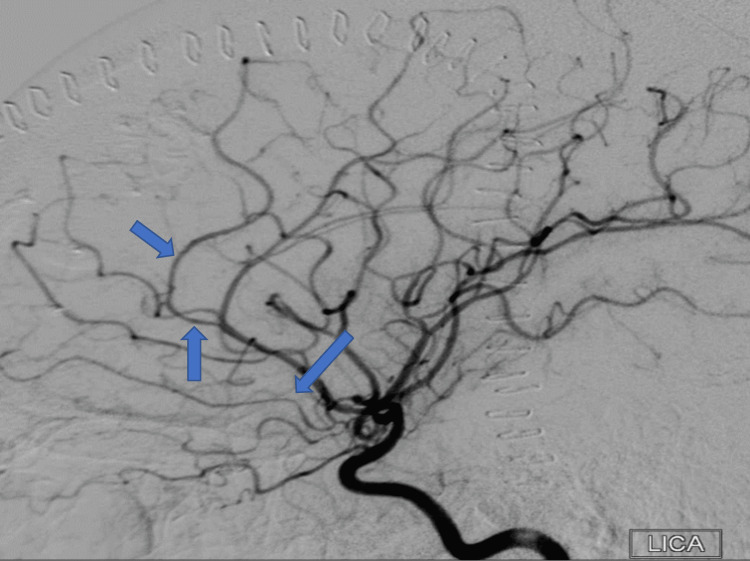

A year after her last outpatient appointment, she presented to the hospital with recurrent episodic thunderclap headaches with associated nausea, vomiting, and photosensitivity. Her neurologic examination was notable for aphasia without notable weakness. In the interim, she had established care with another neurologist who was closer to her home, who had discontinued verapamil and started the patient on venlafaxine for treatment of headaches and mood. CT Head without contrast revealed bilateral SAHs and a left frontal intraparenchymal hemorrhage, approximately 9.4 cc by ABC/2 formula (Figure 3). CTA Head and Neck with contrast again demonstrated multifocal stenosis of intracranial arteries. She underwent a second DSA, which demonstrated multifocal stenosis of intracranial arteries bilaterally (Figures 4–5). Angiogram found diffuse irregularities primarily affecting bilateral anterior cerebral arteries and, to a lesser extent, the bilateral middle cerebral and right superior cerebellar arteries. The patient also underwent brain biopsy with hematoma evacuation. Rheumatological workup was repeated and unremarkable. Lumbar puncture was performed and notable for mildly elevated glucose of 85 (normal range: 50-75 mg/dL) and mildly elevated protein at 46 (normal range: 15-45 mg/dL). Due to concern for PACNS as per discretion of treating physician at that time given the recurrence of symptoms and vascular irregularities, she was administered one dose of high-dose IV methylprednisolone, but this was discontinued when brain biopsy was planned. The biopsied temporal artery, dura, and brain showed no evidence of vasculitis. In the absence of any evidence for an ongoing inflammatory process, verapamil was restarted for symptomatic treatment of suspected recurrent RCVS. It was felt that RCVS was likely precipitated to exposure to SNRI. Venlafaxine was discontinued as this is a known precipitant of RCVS. After clinical improvement, the patient was discharged home and advised to continue verapamil, follow up with vascular neurology outpatient clinic, and undergo follow-up repeat vessel imaging.

Two weeks later, the patient underwent a repeat DSA, which showed interim improvement in multifocal stenosis with near resolution of the stenoses seen in the MCAs (Figures 7–8). During this study, a fistula between the right parietal middle meningeal artery (MMA) and the distal superior sagittal sinus was noted. Approximately four months later, the patient underwent onyx embolization of the MMA-sagittal sinus fistula. At the time of the writing of this article, the patient has not had any further recurrence of vessel irregularities, although she had been admitted for a brief hospital stays with complaint of headaches. Resolution of cerebral vessel irregularities has been confirmed on repeat DSA performed for arteriovenous fistula embolization.